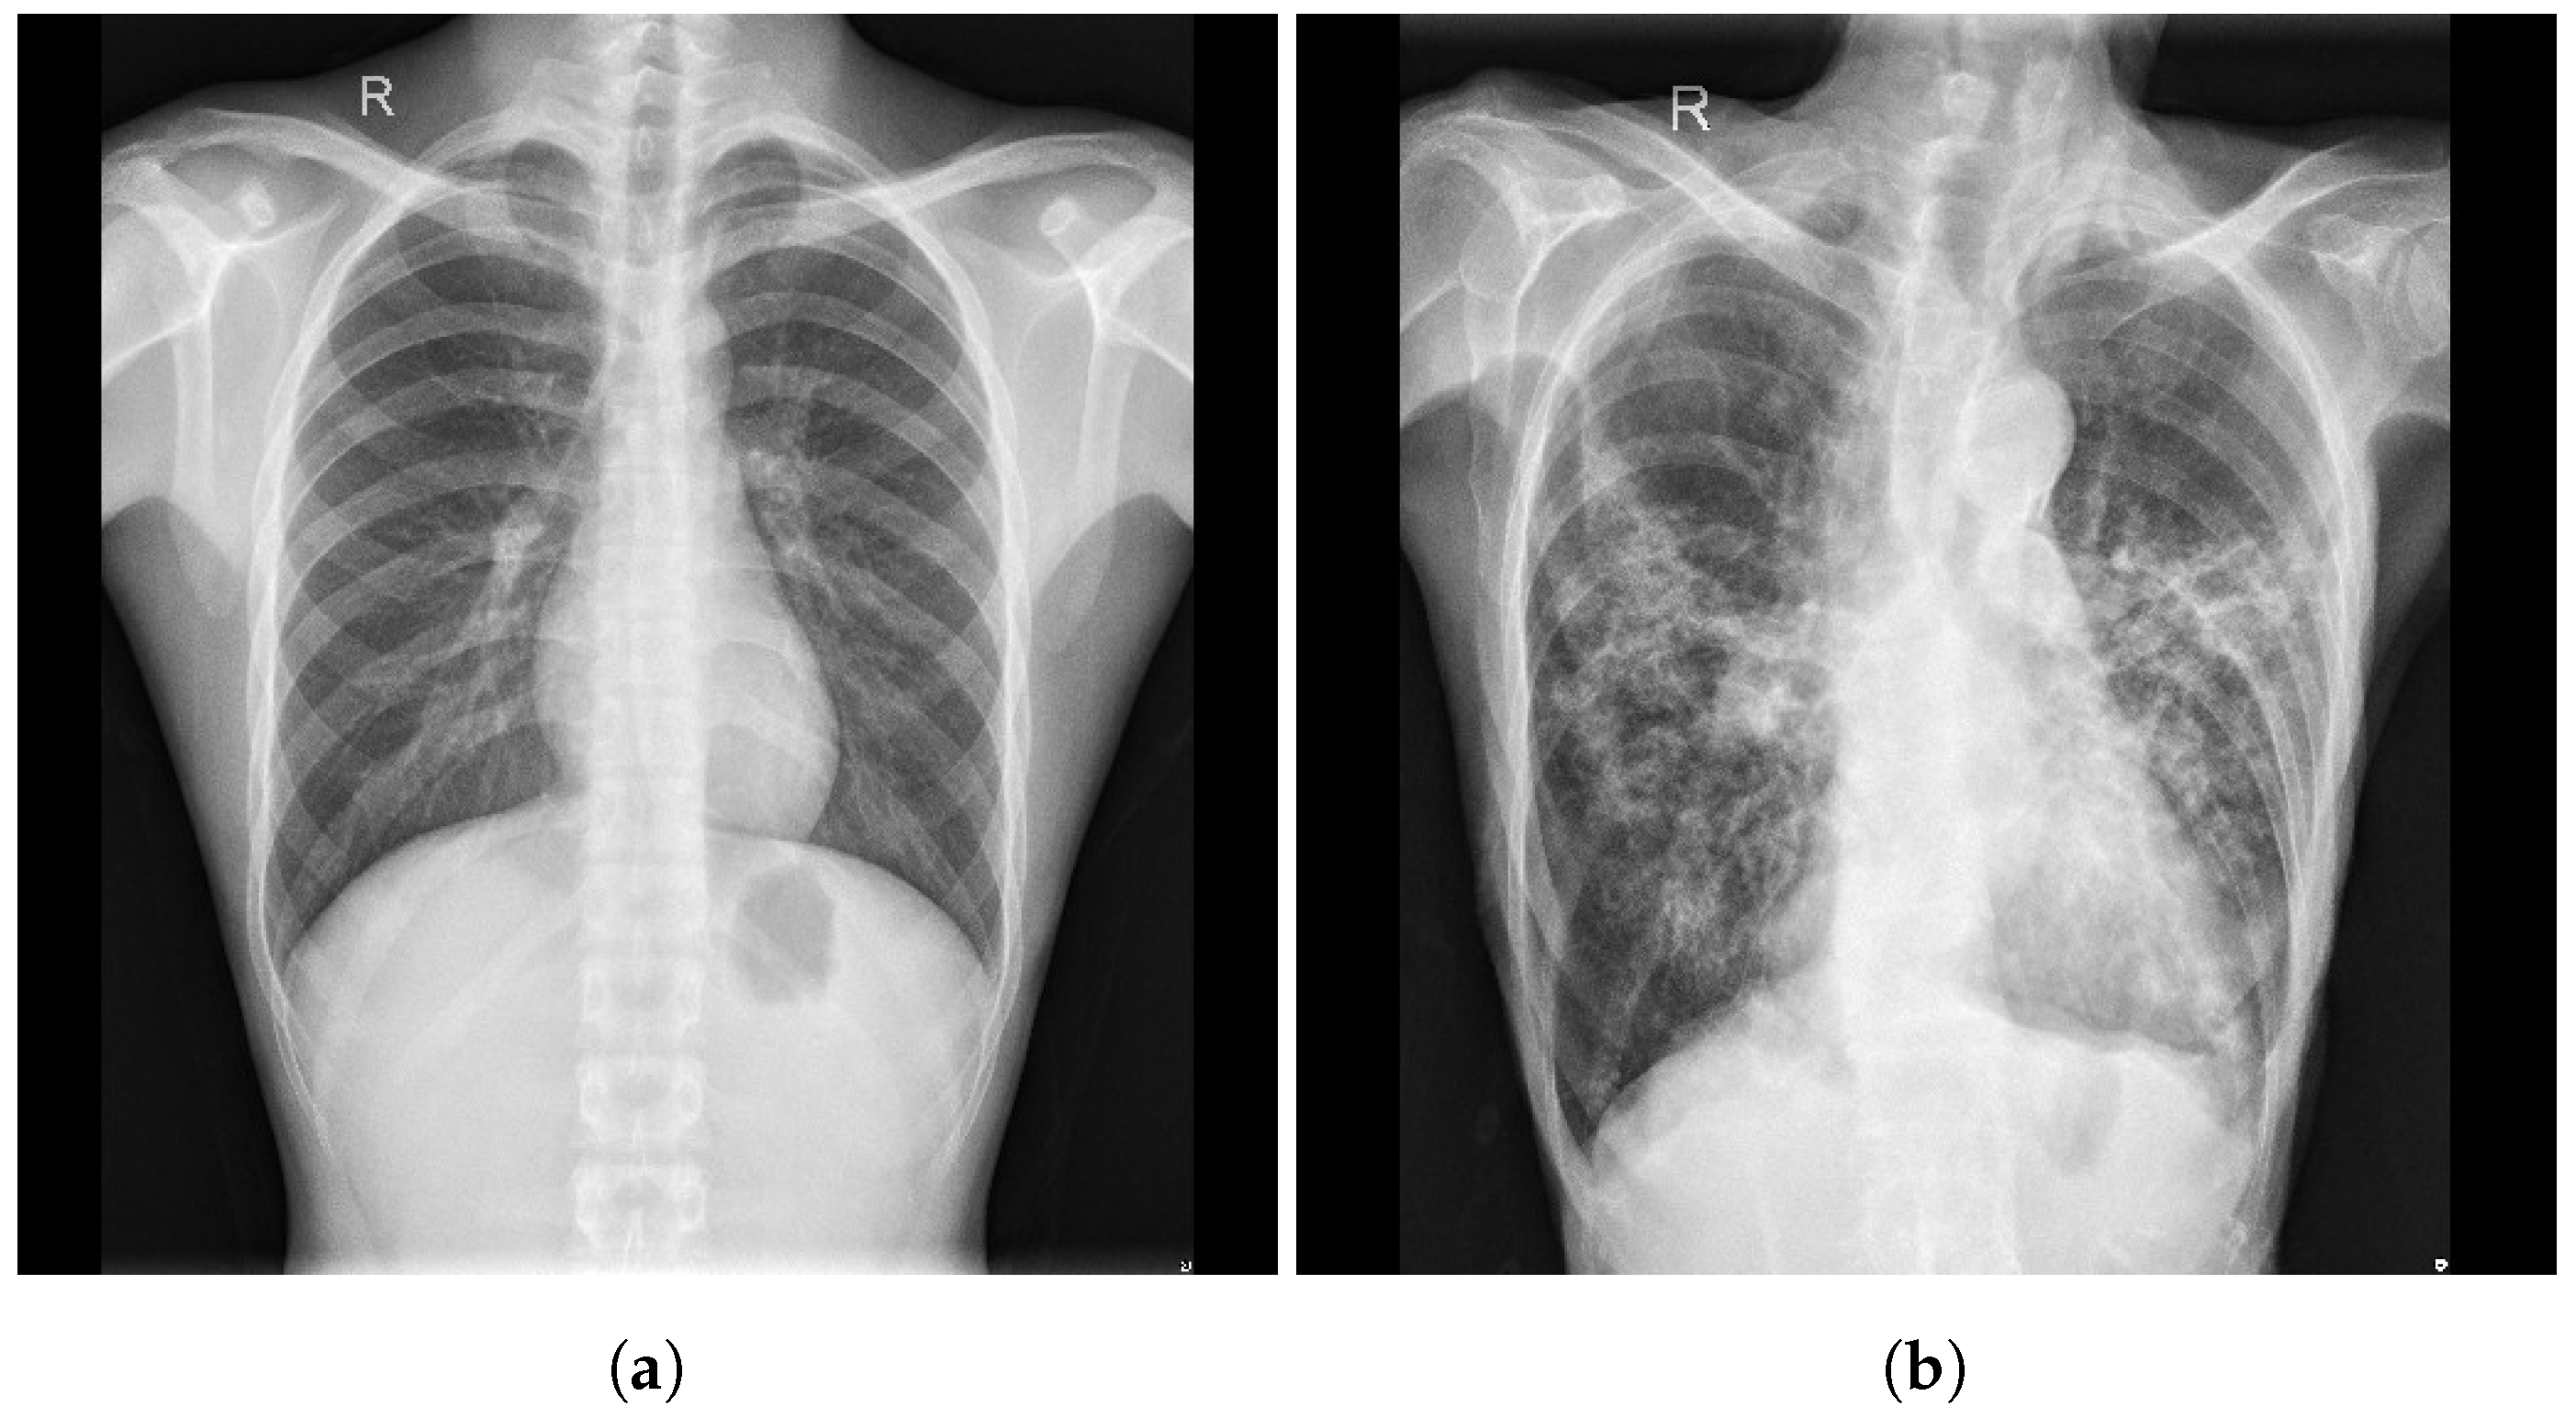

3.6. Montgomery County X-ray

3.7. Shenzhen Hospital X-ray